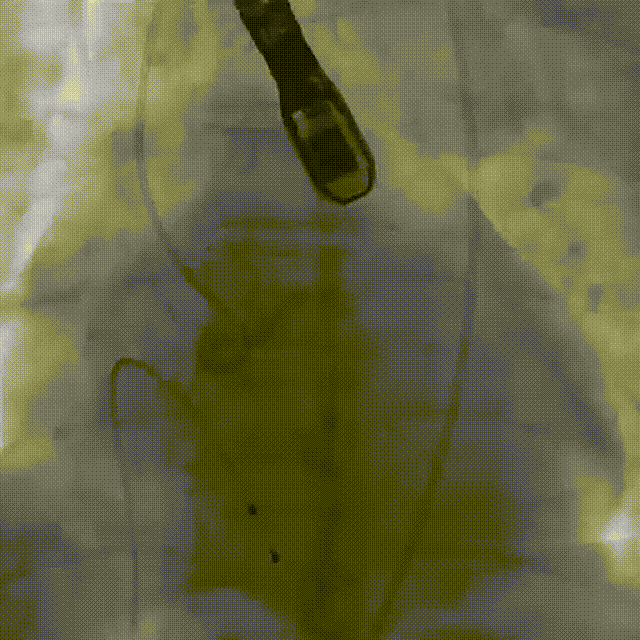

主动脉根部造影

患者全麻,气管插管。经左侧股动脉作为辅入路,将6F猪尾巴导管送至无冠窦窦底,右股动脉作为主入路,右侧股动脉作为主入路,置入18F大鞘,先行主动脉根部造影,可见术前有轻中度返流,行24mm球囊进行预扩,无瓣周漏,无明显腰征,双侧冠脉血流通畅,决定按计划选择27# VitaFlow Liberty™瓣膜,在王建安教授的线上指导、刘先宝教授的现场支持下,将瓣膜释放至功能位,再次造影发现瓣膜位置偏高,遂进行回收,再次释放,最终脱钩,再次造影确认瓣膜位置及形态良好,压差从术前的80mmHg降低至2mmHg,无瓣周漏。